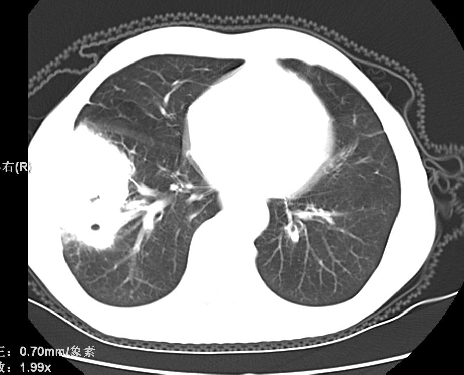

原发性肺癌

内镜提示胃十二指肠溃疡,然而病变来源竟是肺部